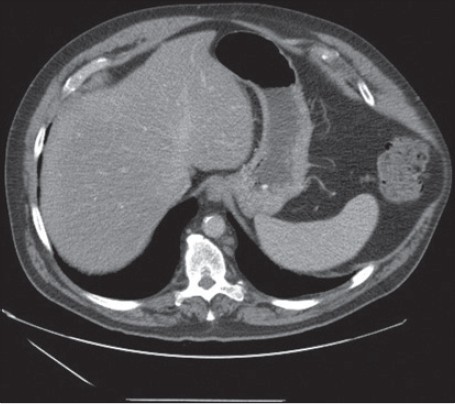

Figure 2: CT of abdomen 10 months after hospital discharge shows left side chest wall hernia through the torn intercostal muscles